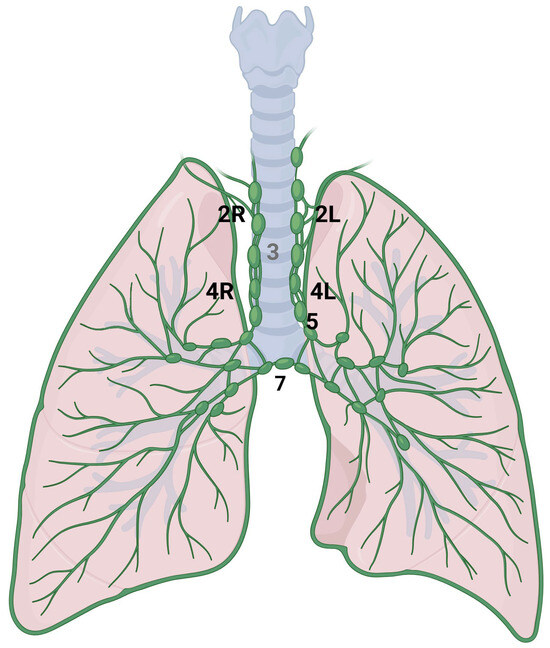

- Rusch, V.W.; Asamura, H.; Watanabe, H.; Giroux, D.J.; Rami-Porta, R.; Goldstraw, P.; Members of IASLC Staging Committee. The IASLC lung cancer staging project: A proposal for a new international lymph node map in the forthcoming seventh edition of the TNM classifica-tion for lung cancer. J. Thorac. Oncol. 2009, 4, 568–577. [Google Scholar] [CrossRef] [PubMed]

- De Leyn, P.; Dooms, C.; Kuzdzal, J.; Lardinois, D.; Passlick, B.; Rami-Porta, R.; Turna, A.; Van Schil, P.; Venuta, F.; Waller, D.; et al. Revised ESTS guidelines for preoperative mediastinal lymph node staging for non-small-cell lung cancer. Eur. J. Cardiothorac. Surg. 2014, 45, 787–798. [Google Scholar] [CrossRef] [PubMed]